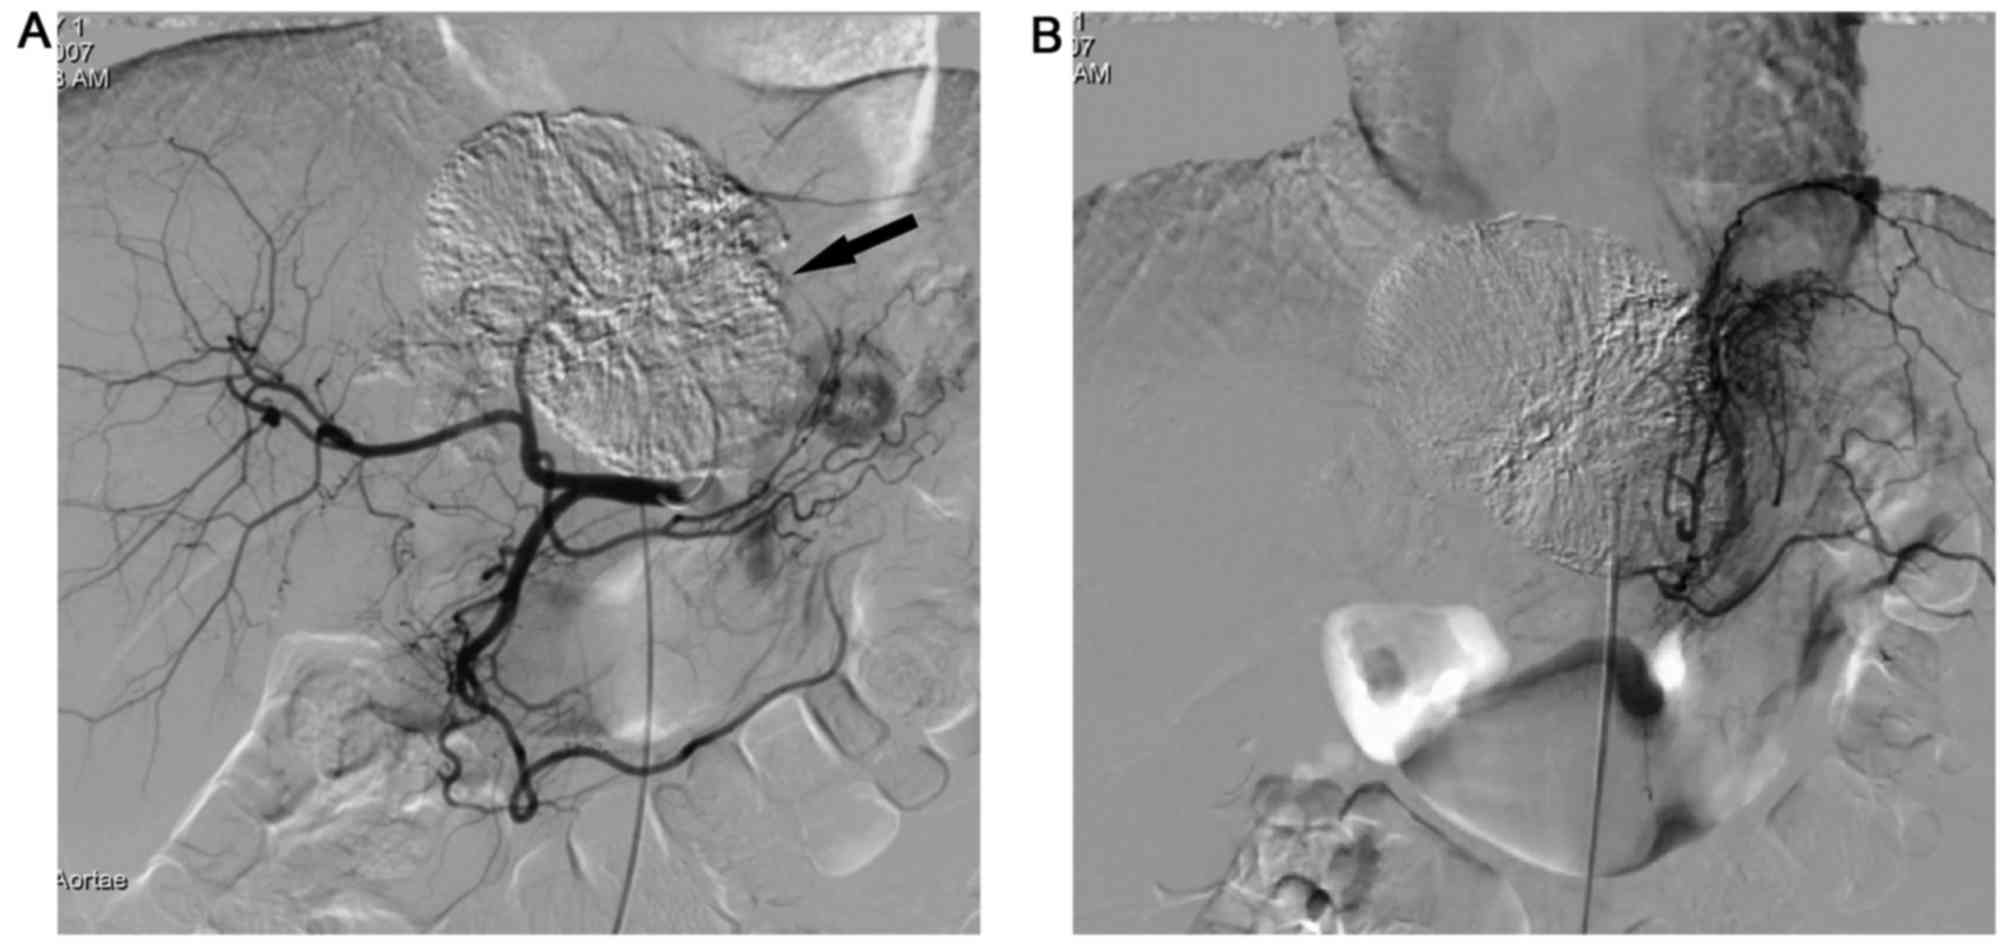

Figure 4.

Images from a 30-year-old man with pedunculated hepatocellular carcinoma who received 4 TACE sessions. (A) Angiography prior to TACE demonstrates an extrahepatic tumor growth in the porta hepatis, taking blood from the right hepatic artery, as the main blood supply, and the gastroduodenal artery. (B) Angiographies taken subsequent to 2 sessions of TACE, revealing that the right hepatic artery functions as the main blood supply, whereas the gastroduodenal artery is complementary. (C) Angiographies taken subsequent to 4 sessions of TACE, demonstrating the same phenomenon as observed in (B), with a nearly complete shrinking of the mass. TACE, transcatheter arterial chemoembolization.

All angiographies revealed that the intrahepatic arteries served as the main blood supply for P-HCC, whereas the extrahepatic collateral arteries served complementary functions in P-HCC, regardless of whether the patient was pre- or post-TACE (Figs. 1–4). Additionally, P-HCC tumor lesions were prone to acquire parasitic blood supplies from adjacent vessels following repeated TACE (Figs. 2 and 5).